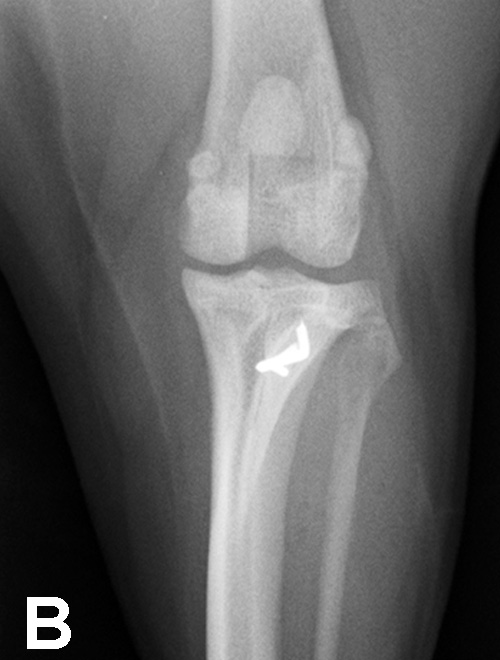

This pathology has a multifactorial etiology that affects the coxofemoral joint, most commonly in large-breed dogs (especially the German shepherd dog), but can also affect small-breed dogs and cats. Genetic and environmental factors can lead to joint laxity, which subsequently causes abnormal development of the acetabulum and femoral head, ultimately resulting in OA. Diagnosis in young patients is based on clinical signs (eg, difficulty in rising, swinging of the hindlimbs, pain, subluxation and laxity of the femoral head [Ortolani test]). Radiographic findings that confirm hip dysplasia are joint subluxation, incongruency, and early degenerative changes (Figure 1).

Figure 1. Ventrodorsal radiograph of the pelvis in a 12-month-old Labrador retriever with bunny-hopping and pain on extension of the hips. Bilateral coxofemoral subluxation and mild OA are evident.